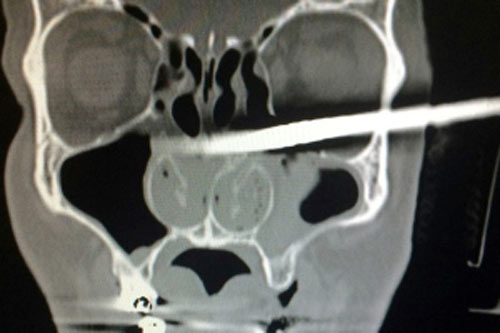

Một người đàn ông Ba Lan bị thanh ngỗ đâm xuyên mặt nhưng vẫn đi bộ đến bệnh viện cấp cứu khiến các bác sỹ ở đây hết sức ngạc nhiên.

Kamil Podwinski, 40 tuổi, đang sửa nhà ở thành phố Konin, tỉnh Wielkopolskie thì vô tình bị trượt chân và rơi trúng một thanh gỗ nhọn.

Mũi nhọn của thanh gỗ này đâm vào dưới hốc mắt và xuyên thẳng qua sau cổ anh.

Tại bệnh viện, các bác sỹ không thể di chuyển được đầu anh để chụp X-quang vì thanh gỗ quá dài và to. Bối rối trong việc xử lý, phía bệnh viện yêu cầu lực lượng cứu hỏa xử lý vì họ sợ rằng họ sẽ khiến vết thương trở nên trầm trọng hơn nấu cố gắng lấy thanh gỗ ra ngoài.

Kết quả chụp X-quang

Hiện anh Kamil đang phục hồi sức khỏe. Các bác sỹ tại bệnh viện cho biết, thanh gỗ không làm hỏng mắt nạn nhân và gây các tổn thương quá nghiêm trọng".